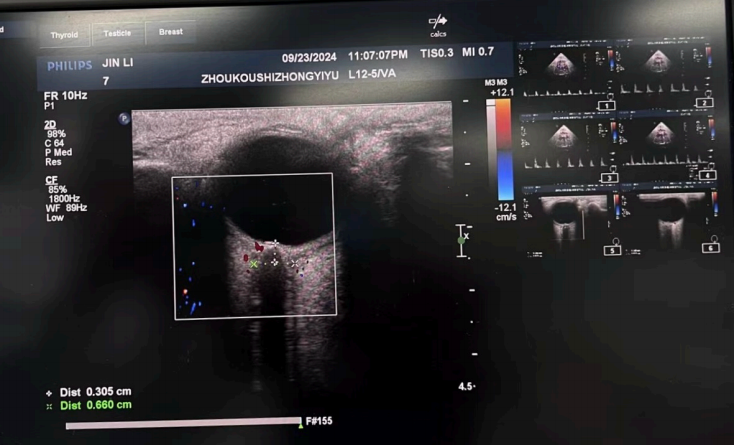

圖3:視神經(jīng)鞘直徑ONSD:評(píng)估顱腦?腫(操作者:吳威)